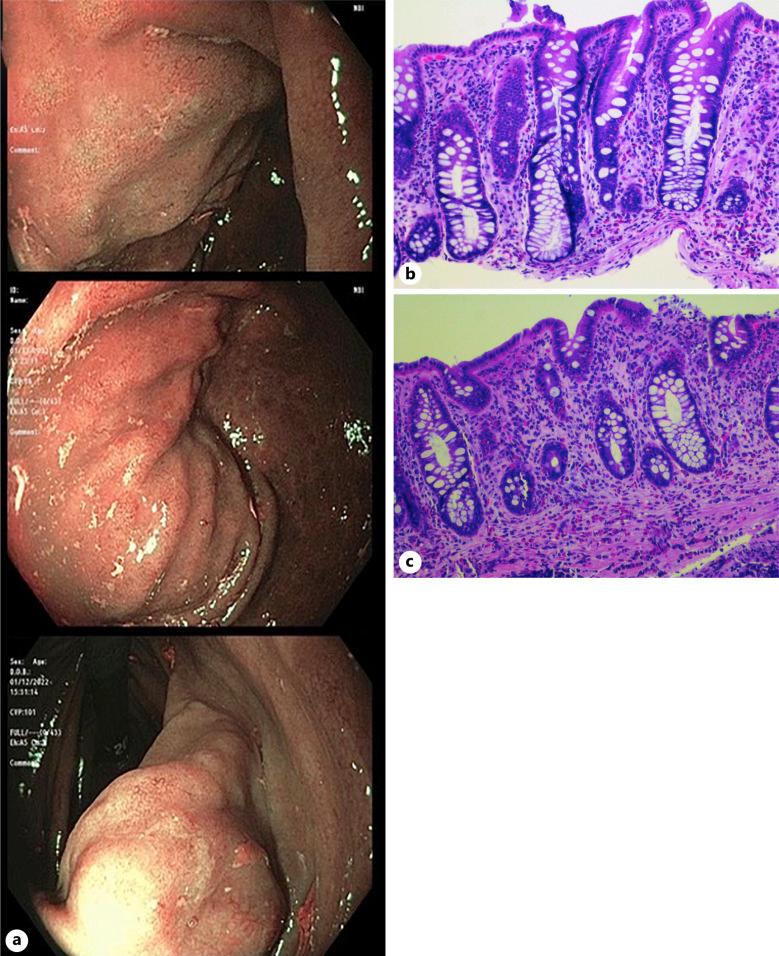

CASE PRESENTATION

In this case report, we describe the case of an asymptomatic and immunocompetent Liberian patient with gastroduodenal strongyloidiasis whose diagnosis was based on histologic findings during endoscopic evaluation for iron deficiency anemia.

在本病例报告中,我们描述了一例无症状且免疫功能正常的利比里亚患者,其患有胃十二指肠类圆线虫病,诊断基于缺铁性贫血内镜评估期间的组织学发现。